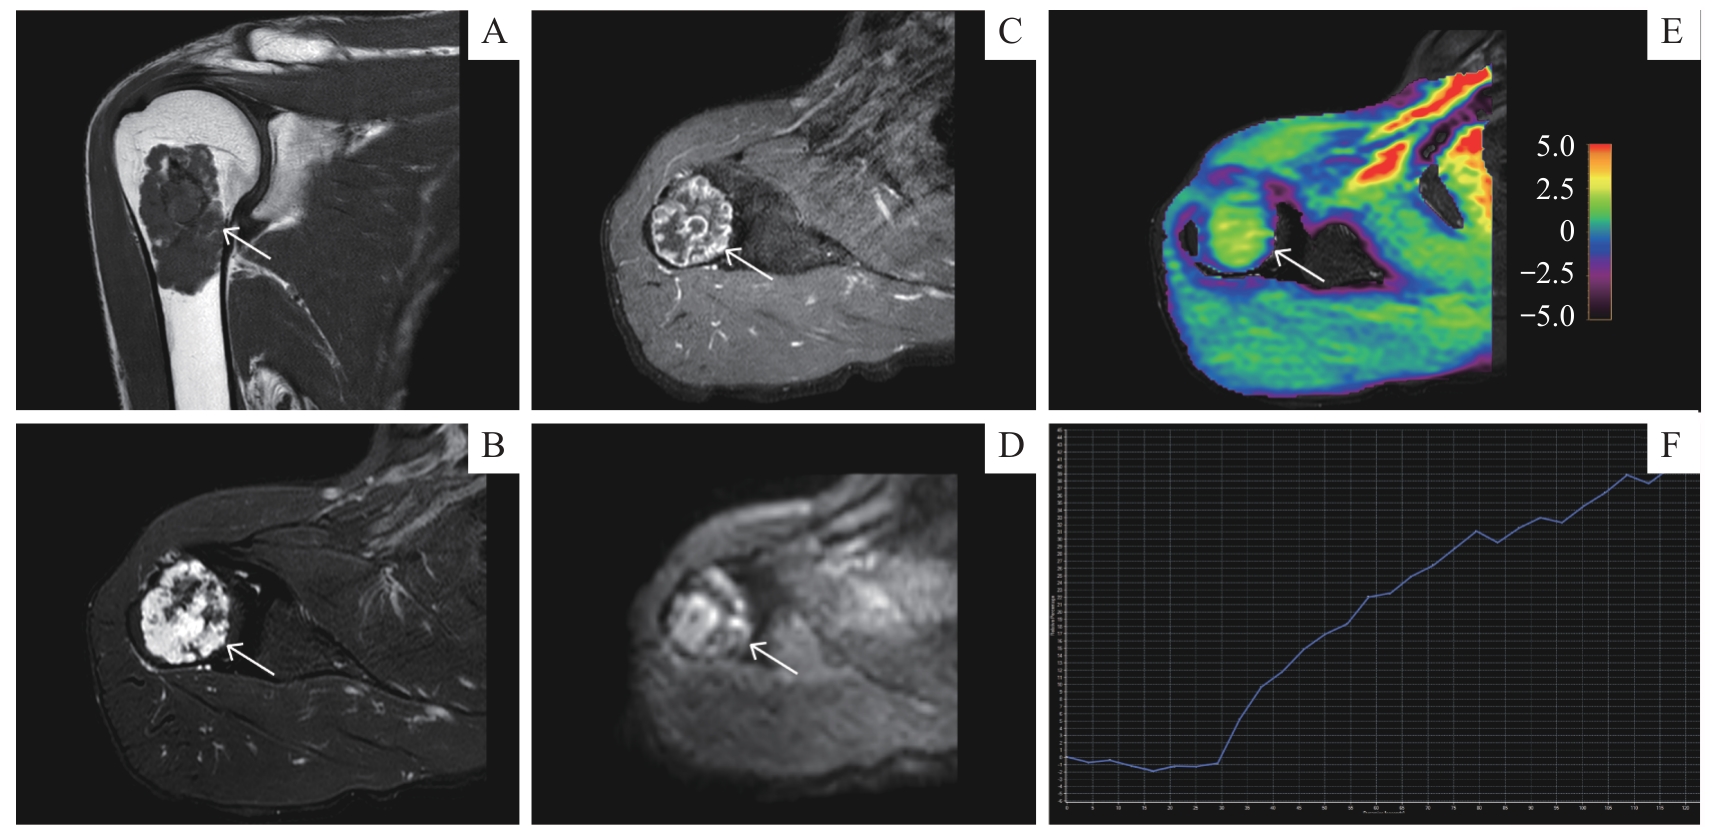

| 图4 APTw成像在恶性骨肿瘤中的应用 Note: A 52-year-old male with chondrosarcoma of the right humerus. A. Coronal T1-weighted MRI sequence. B. Axial T2-weighted fat-saturated MRI sequence. C. Axial contrast-enhanced T1-weighted MRI sequence. D. Axial DWI ( b=1 000 s·mm -2) sequence. E. Axial APT image fused with axial T2WI (the color bar indicates the APT values). F. TIC classification (type Ⅰ). |

| Fig 4 Application of APTw imaging to malignant bone tumor |